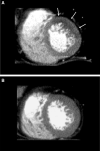

Myocardial ischemia is caused by a mismatch between myocardial oxygen consumption and oxygen delivery in coronary artery disease (CAD). Stratification and decision-making based on ischemia improves the prognosis in patients with CAD. Non-invasive tests used to evaluate myocardial ischemia include stress electrocardiography, echocardiography, single-photon emission computed tomography, and magnetic resonance imaging. Invasive fractional flow reserve is considered the reference standard for assessment of the hemodynamic significance of CAD. Computed tomography (CT) angiography has emerged as a first-line imaging modality for evaluation of CAD, particularly in the population at low to intermediate risk, because of its high negative predictive value; however, CT angiography does not provide information on the hemodynamic significance of stenosis, which lowers its specificity. Emerging techniques, e.g., CT perfusion and CT-fractional flow reserve, help to address this limitation of CT, by determining the hemodynamic significance of coronary artery stenosis. CT perfusion involves acquisition during the first pass of contrast medium through the myocardium following pharmacological stress. CT-fractional flow reserve uses computational fluid dynamics to model coronary flow, pressure, and resistance. In this article, we review these two functional CT techniques in the evaluation of myocardial ischemia, including their principles, technology, advantages, limitations, pitfalls, and the current evidence.